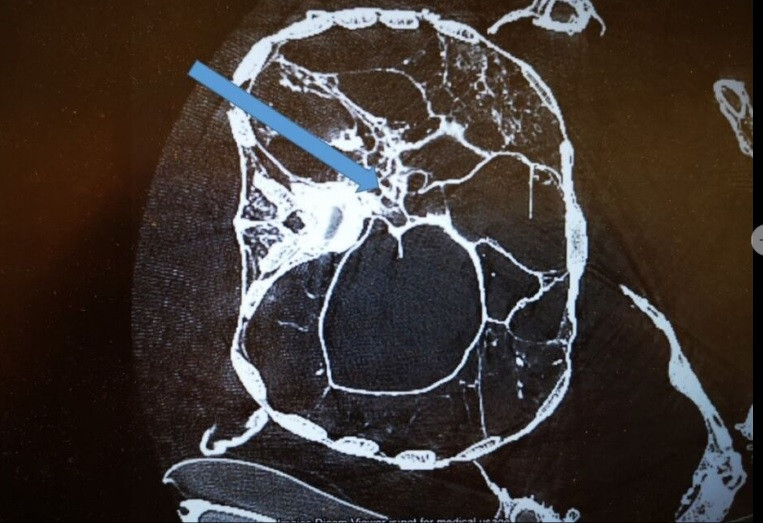

Từ các đặc điểm xương và kết quả phân tích xác ướp bằng phương pháp chụp cắt lớp vi tính 3D (3D-CT), nhóm nghiên cứu ước tính người đàn ông qua đời khi khoảng 20 - 25 tuổi, cao khoảng 1,72m.

Cụ thể, kết quả phân tích bằng 3D-CT chỉ ra người đàn ông trên tử vong do cú đánh chí mạng vào đầu và bị đâm vào lưng trong lúc đang đứng hoặc quỳ. Những vết thương nghiêm trọng này gây ra bởi một hoặc hai kẻ tấn công vào khoảng năm 996 - 1147.